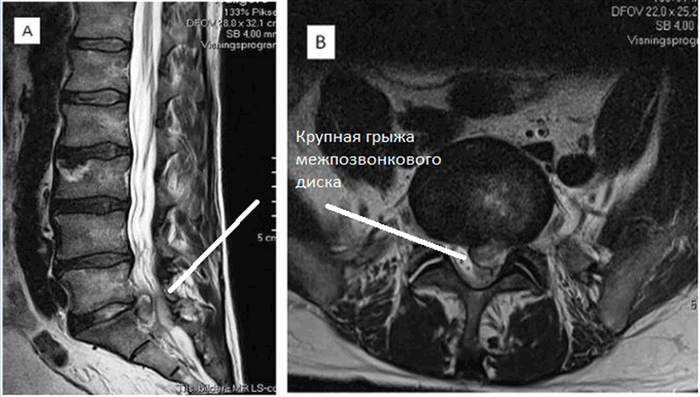

МРТ пояснично-крестцового отдела позвоночника показывает грыжевое выпячивание диска на уровне 5 поясничного и 1 крестцового позвонка, которое оказывает давление на спинной мозг и нервные корешки.